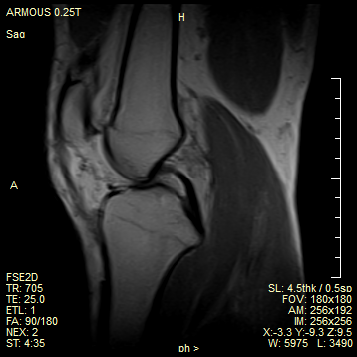

负重扫描 支持科研

通过负重位扫描,可及时发现膝关节置换术后负重状态下产生的偏移,传统磁共振扫描死角得以解决

媲美高场 高效诊疗

成像效果媲美高场强设备,完全满足骨科诊断需求